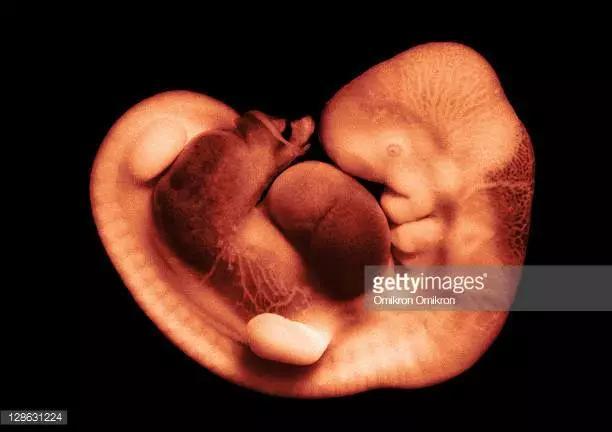

在受精卵发育过程中,最初两周称为孕卵。然而随着时间的推移,各种器官的逐渐形成,在孕8周以前,称为胚胎(或胎芽);妊娠三周至妊娠第一个月四周称为胎芽期,胎芽身长0.5—1厘米状如小海马。

怀孕的第一个月为胎芽期,新的生命在此时期的生长速度是其一生中最快的。

第四周,胚泡已牢固地植入子宫里,在这个时期胎儿神经系统、血液循环器官的原型几乎都已出现,肝脏从这个时期开始有明显发育;眼睛和鼻子的原型还未生成,但嘴和下巴的原型已能看到;与母体相连的脐带也从这个时期开始发育。

在怀孕三十多天以后,各原始细胞进行分化,慢慢形成胎芽,胎芽进一步发展形成胎心,到孕9周胚胎完全成为胎儿并慢慢发育长大,所以医学上称孕9周前为胚胎,9周以后就称为胎儿。孕十个月脱离母体正式来到人世间,这就是一个新生命形成的过程。